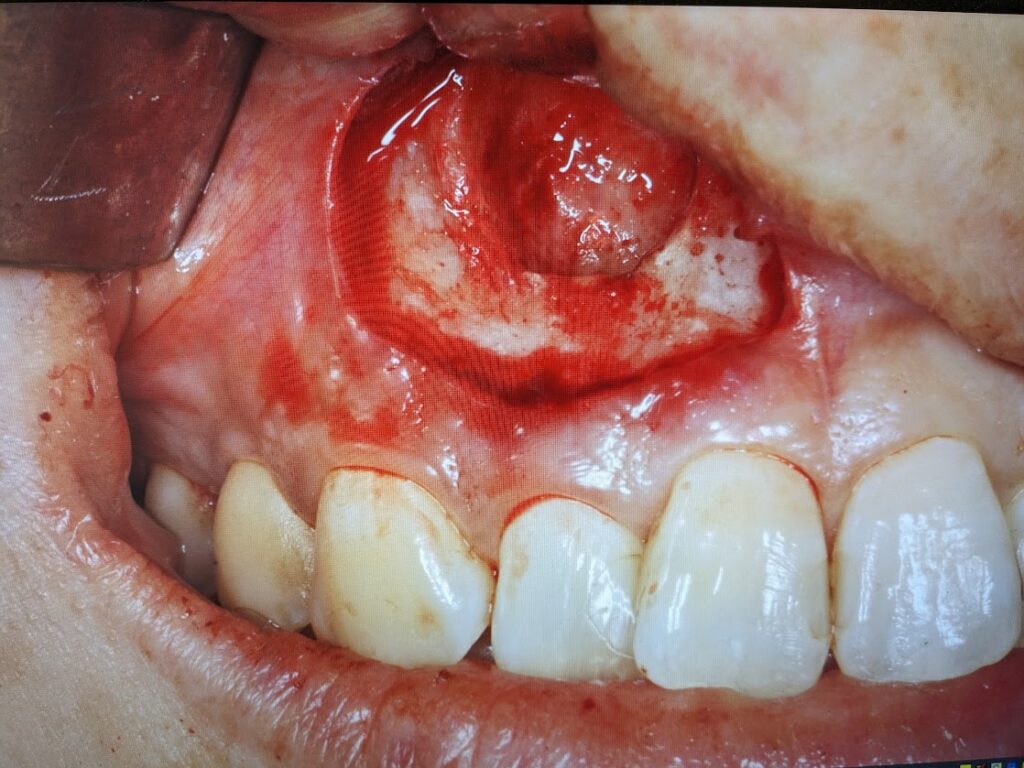

嚢胞壁は菲薄化した部分が裂けると中の膿が排出されるため縮小します。

嚢胞を摘出しますと、原因である右上2の歯根が露出されます。

露出した歯根は切断し摘出します。切断面はセメントかスーパーボンドにて被覆します。(歯根端切除術)

歯根を切断しますと大きな洞穴(嚢胞腔)をみとめます。この中に残留異物がないか良く掻爬して確認します。